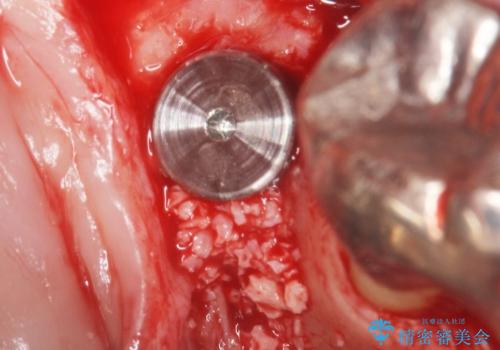

- 奥歯のインプラントをご希望し来院された患者様です。

骨が少なく下顎神経に近いことから、他院でインプラントできないと言われたとのことでした。

骨増生(GBR)を行い骨を増やすことでインプラント治療を可能にしました。